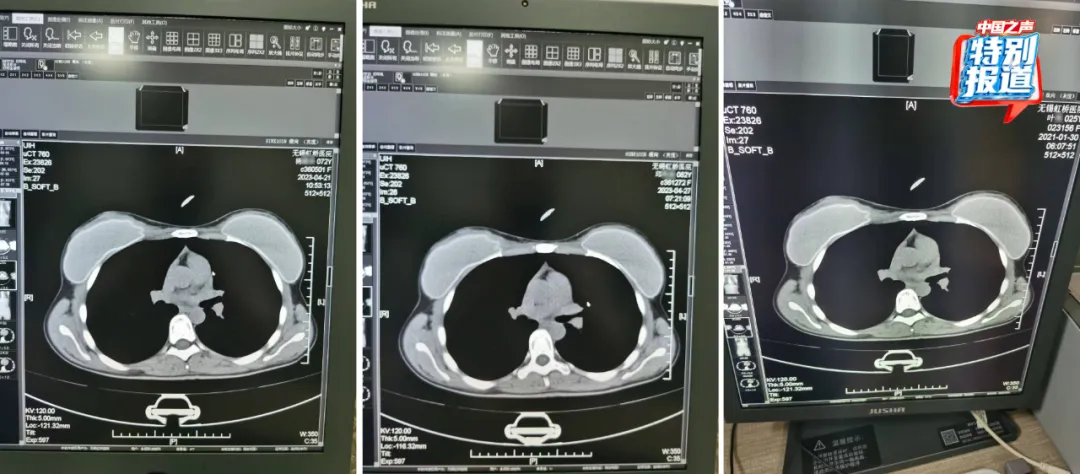

在被举报的病历中,杨某某(72岁)和邱某某(62岁)的病历里,有根据所拍片子的情况做出的诊断,却找不到对应的影像。6月份又查到了她们的CT影像,片子上清晰看出,两位患者的吊坠形状、大小和位置都基本一致 。

不仅这两位患者CT影像类似,朱成刚比对发现,2021年做过CT的25岁女性叶某的片子上,也有看起来极为相似的吊坠,肉眼看,三人的片子几乎一模一样。

△72岁的杨某某、62岁的邱某某与25岁的叶某,三人的片子几乎一模一样。